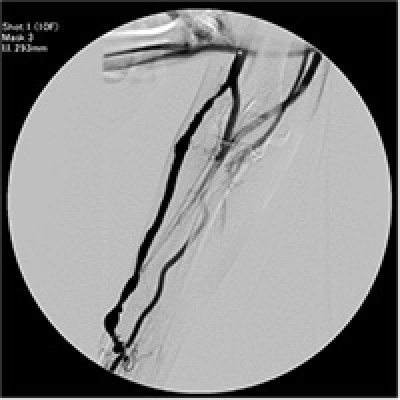

左の写真はPTA前の造影検査の写真です。黒く写っているのが、シャントになります。真ん中の写真では、狭い部分に対し、バルーン(風船)を膨らませて、血管を広げています。右の写真はPTA後の造影検査の写真です。

放射線を用いる場合は「手技が容易であり、再現性に優れ、治療中の血管破裂などのリスクが少ない」「シャント全体の評価が容易」などのメリットはありますが、「造影剤を使用するために、喘息などのアレルギーがある患者様には使用ができない」「放射線による被ばくの恐れ」があるなどのデメリットがあります。

放射線による被ばくは「放射線を使用する時間をできるだけ短くする」「放射線を使用する範囲を小さくする」「防護具を付ける」などによって、被ばく量を減らすようにしています。

超音波を用いる場合は「放射線被ばくがない」「アレルギーのある患者様にも使用できる」などのメリットはありますが、「手技が難しく、再現性が得られにくいために治療評価が難しい(=患者様も理解しにくい)」「出血など合併症に対応するのが遅れる可能性がある」「鎖骨下などの中心静脈の評価ができない」などのデメリットがあります。

それぞれ一長一短ですので、それぞれの状況に応じて対応することとしています。